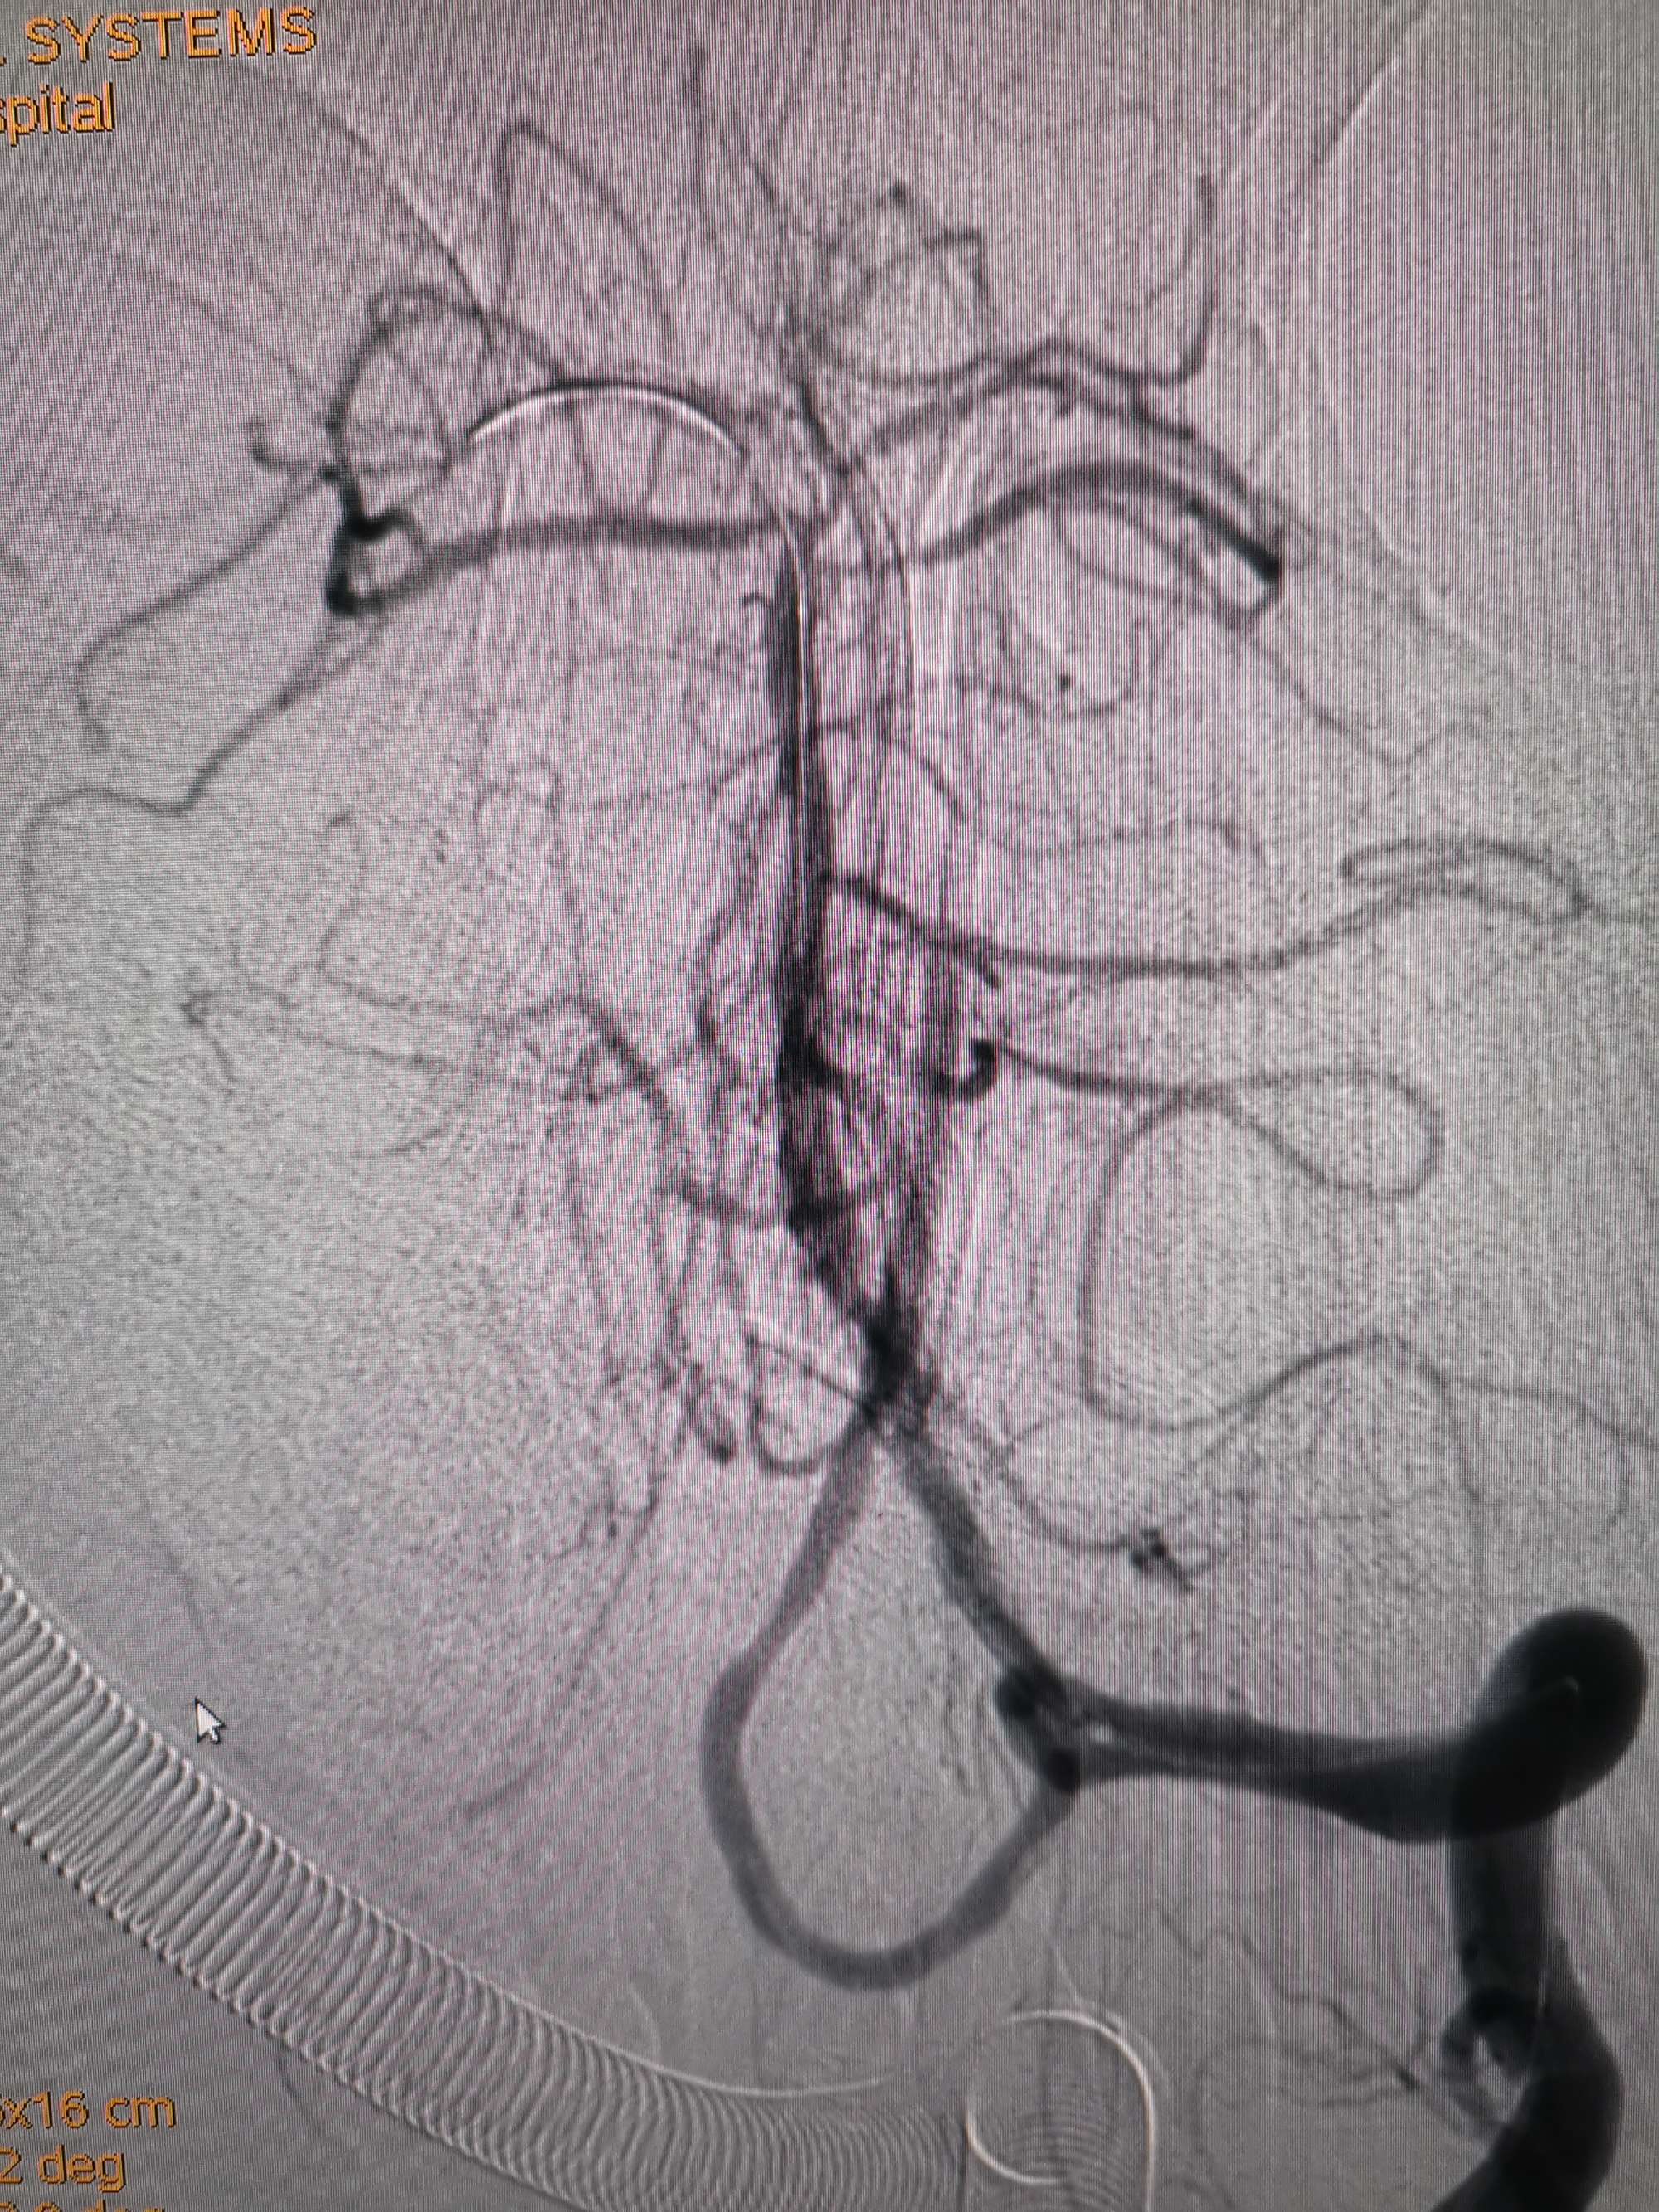

入院造影影像